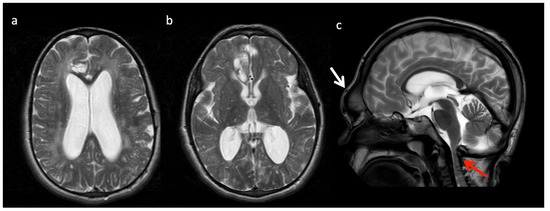

Mucopolysaccharidoses (MPS) (Figure 11): MPS are a group of lysosomal storage disorders that demonstrate characteristic though inconstant MR features of enlarged perivascular spaces, cerebral white matter hyperintensity on T2/FLAIR, and ventriculomegaly [8]. Spinal imaging shows a dysostosis multiplex. MRS can demonstrate elevated Cho (gliosis and demyelination) and peaks at 3.6–3.7 ppm from mucopolysaccharides accumulated in the brain [3].

Figure 11.

Thirteen-year-old male with Hurler’s disease (mucopolysaccharidosis). (a,b) Axial T2W at the level of the corona radiata (a) and third ventricle (b) show diffuse white matter hyperintensity, multiple enlarged perivascular spaces, and generalized ventriculomegaly. Volume loss in the right frontal lobe may be due to prior injury. (c) Sagittal T2 images from a different 13-year-old male with Hurler’s shows frontal bossing (white arrow), dens hypoplasia, platyspondyly, J-shaped sella, and thickened dural ring at the foramen magnum with craniocervical junction (CVJ) stenosis (red arrow).